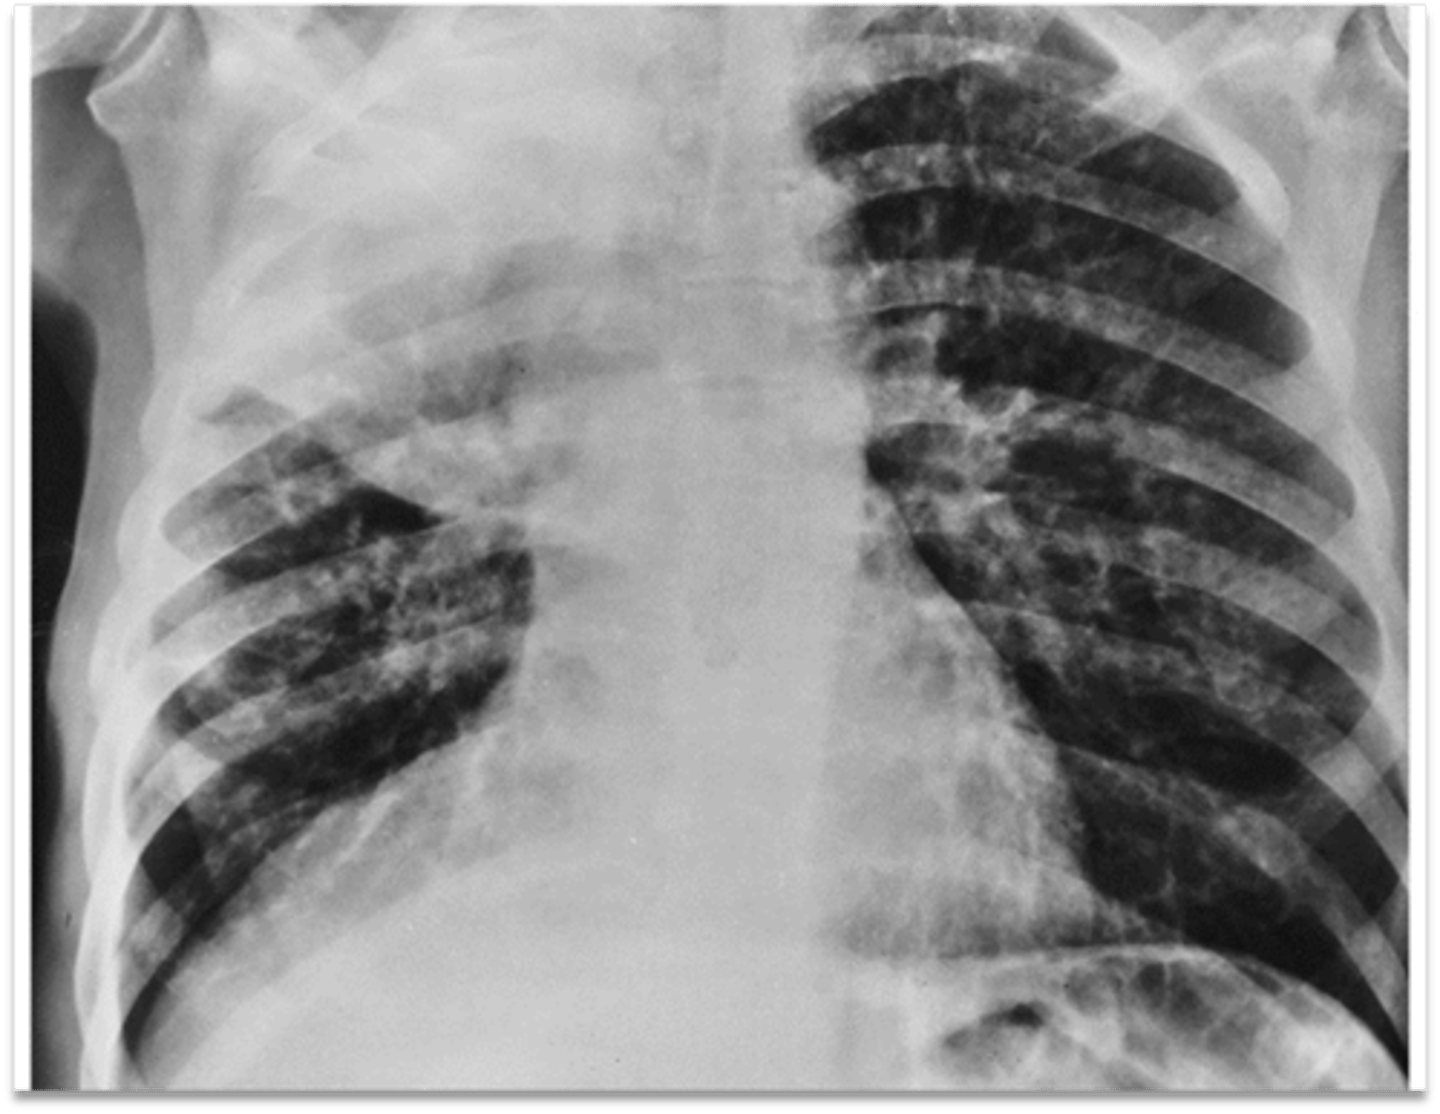

Atelectasis (collapsed area looks white and a tracheal shift)

Interpretation?

Pneumothorax (dark black area with no vessels)

Interpretation?

Tension pneumothorax (tracheal shift and lung shrunk)

Interpretation?